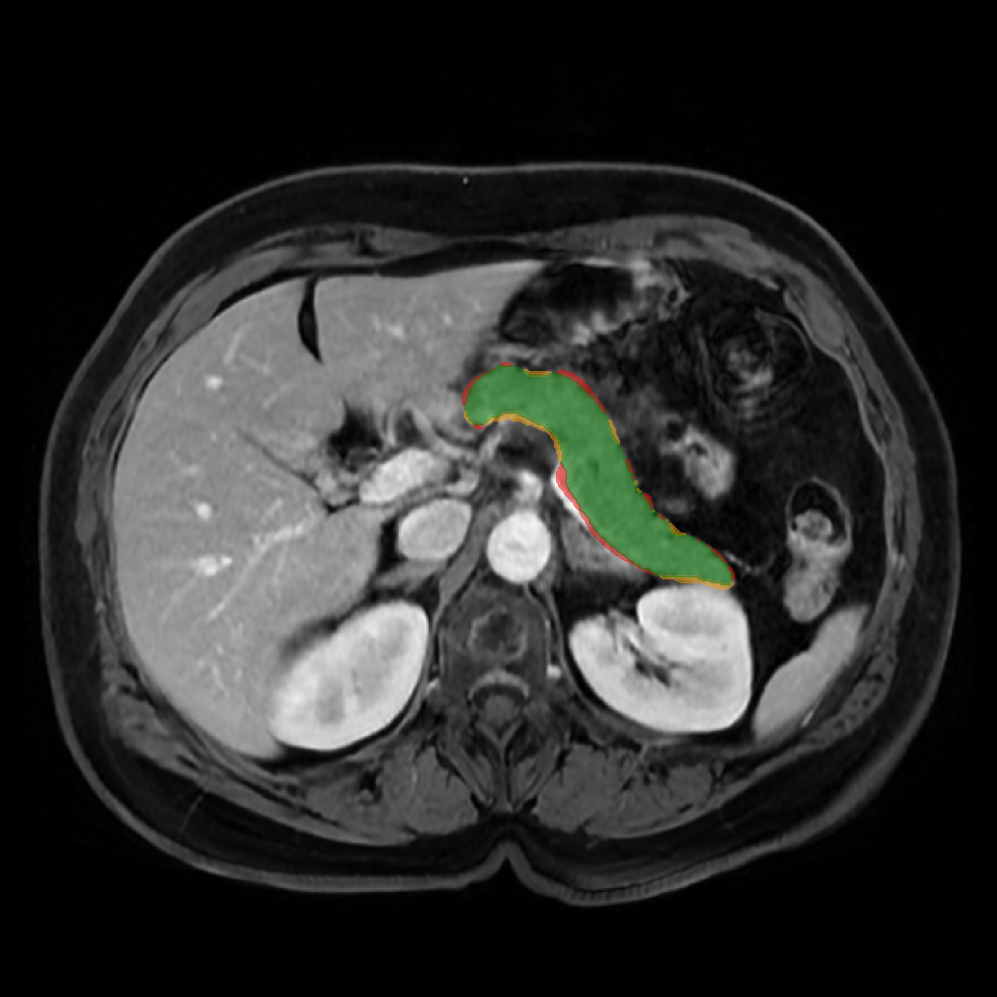

Accurate pancreas segmentation is a critical prerequisite for precise cyst analysis and classification. Recently, we developed PanSegNet [zhang2025large], a novel segmentation architecture incorporating linear self-attention layers [zhang2022dynamic] within the nnUNet framework [isensee2021nnu] to enhance global information modeling capabilities while maintaining computational efficiency (Fig. 1). PanSegNet demonstrated exceptional segmentation performance across both T1W and T2W modalities, achieving mean dice scores of 86.817.30% and 89.626.38%, respectively (Table 1, Fig. 2b-c). This performance significantly exceeded that of Swin-UNETR [hatamizadeh2021swin], one of the most used state-of-the-art transformer-based medical segmentation models, which achieved dice scores of 79.091.40% and 76.290.66% for T1W and T2W, respectively (). In this study, we integrated PanSegNet into our Cyst-X engine along with a classifier for risk prediction. In Section 2.2, we show that the choice of segmentation model affects the classification results. The performance advantage of PanSegNet was consistent across all seven medical centers, demonstrating robust generalization despite variations in imaging protocols and equipment (Table 1). This cross-institutional reliability is particularly important for clinical applications, where model performance must remain consistent regardless of imaging site or acquisition parameters.

2.2.1 Importance of accurate pancreas segmentation in classification

To assess the importance of accurate pancreas segmentation in classification, we evaluated how different ROI sources affect DenseNet-121’s performance. Specifically, we compared classification results using ROIs generated by PanSegNet and Swin-UNETR, both under centralized learning, against a baseline using radiologist-defined ROIs. As shown in Table 2, using PanSegNet’s masks resulted in only a modest performance decline, reflecting its strong segmentation quality. In contrast, Swin-UNETR led to a more substantial drop, demonstrating that inferior segmentation can directly compromise classification. For 3-class classification, the mean AUC dropped from 75.59% (radiologist ROI) to 72.26% with PanSegNet, and further to 66.95% with Swin-UNETR on T1-weighted images. On T2-weighted scans, the AUC declined from 81.09% to 74.18% (PanSegNet) and to 69.63% (Swin-UNETR). A similar trend was observed in 2-class classification: on T1W, AUC dropped from 78.13% to 74.84% (PanSegNet) and 70.20% (Swin-UNETR); on T2W, from 82.37% to 77.01% and 68.92%, respectively. These results emphasize that accurate segmentation—particularly via PanSegNet—is not only essential for volume estimation but also critical to preserving downstream classification performance in the Cyst-X pipeline.

Each patient was categorized into one of these three ground truth classes: no risk/control, IPMN low-risk, or IPMN high-risk. To evaluate variability in image acquisition, we applied uniform manifold approximation and projection (UMAP) to image quality indicators, revealing distinct clustering patterns by imaging center and slice thickness. This heterogeneity reflects real-world clinical variability, enhancing the dataset’s generalizability while presenting technical challenges for model development. Fig. 6 shows examples of low-grade, high-grade, and cancer developing IPMNs from the Cyst-X dataset.